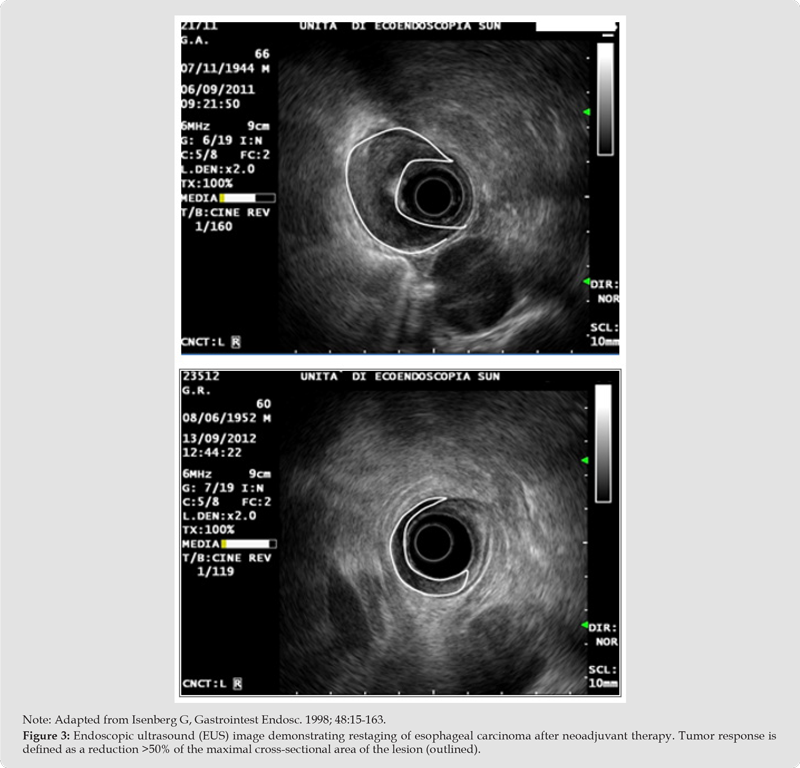

EUS-guided biliary drainage (EUS-BD) is recommended over percutaneous drainage after failing ERCP by ESGE guidelines [9]. Meta- analyses confirm high technical (~97%) and clinical (~91%) success [10-12]. Comparative studies consolidate EUS-BD as the preferred rescue strategy [13,14]. For pancreatic fluid collections, EUS-guided drainage using LAMS is now standard, with success rates >90% [12,15]. Studies suggest that coaxial double-pigtail stents (DPPS) within LAMS may reduce bleeding and occlusion [13-15]. EUS-guided celiac plexus neurolysis provides effective pain relief in pancreatic cancer, while investigational approaches include brachytherapy, fiducial placement, and ablation techniques [20] (Figure 3).